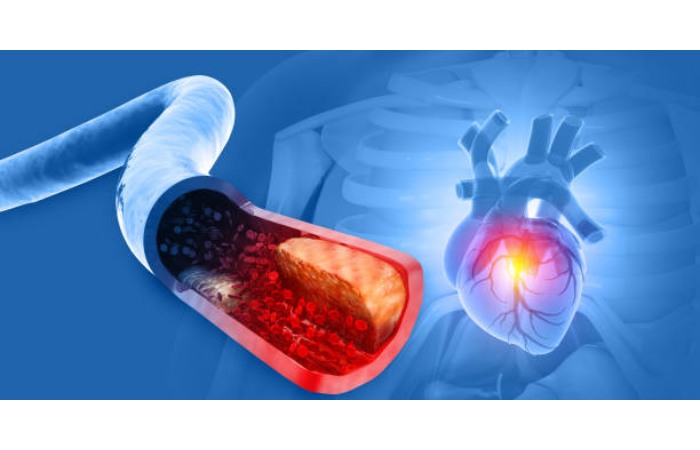

Cardiovascular disease is a general term cast-off to describe conditions that affect the heart’s or blood vessels’ health. Many health problems associated with heart disease are related to atherosclerosis, or the buildup of plaque on the walls of the arteries. In people with heart disease, the buildup can be central to blood clots, which can block blood movement and cause a heart attack or stroke.

Numerous scientific studies have shown that air contamination can worsen existing cardiovascular disease and contribute to the development of the disease. The evidence is robust for exposure to outdoor particulate pollution. Delicate particulate matter (particles smaller than 2.5 µm in diameter, or PM2.5) can increase the risk of cardiovascular events.

Research by the EPA and others has found that exposure to higher concentrations of PM2.5 for just a few times or weeks can trigger heart attacks and cardiovascular disease-related deaths. Long-term exposure can lead to an augmented risk of circulatory mortality and a reduced life expectancy.

For the individual, the risk of cardiovascular disease from particulate pollution is lower than the risk from many of the other well-established risk factors described above. However, for the general population, short- and long-term exposure has been shown to increase hospitalizations for serious circulatory events, such as coronary syndrome, arrhythmia, heart failure, stroke, and sudden cardiac death, particularly in people with established heart disease.